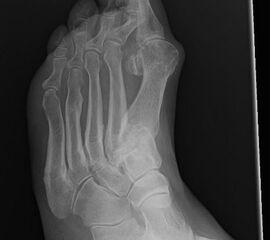

Eine Röntgenaufnahme unter Belastung mit Abbildungen des ganzen Fußes a. p. (mit 15-20° Röhrenkippung) und seitlich, sowie Schrägaufnahmen, reichen meist zur Diagnose. Manchmal ist ein MRT und DVT ergänzend hilfreich. Selten wird die Indikation für ein SPECT CT gestellt (Abb. 6).

• konventionelle Röntgenbilder mit Belastung im Stehen a. p. und seitlich, ggf. schräg (Abb. 9, 10 und 11).

Es gibt neben der Möglichkeit mit der in situ TMT II, III Arthrodese auch die Möglichkeit Fehlstellungen wie den Pes metatarsus adductus zu adressieren (Abb. 9 und Abb. 24 zeigen das prä- und postoperative Röntgenbild eines Patienten mit Pes adductus Korrektur).

• Röntgenkontrolle nach 8-10 Wochen, dann - je nach knöchernem Durchbau - Übergang zur Vollbelastung im Konfektionsschuh (Abb. 24 und 25).